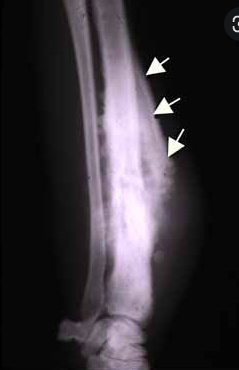

How can you spot osteosarcoma on an X-ray?

A

1. ill-defined lesion with an indistinct zone of transition

2. sclerotic or lytic areas within the lesion

3. cortical destruction

4. codman triangle

5. sunray spicules

What is codman triangle?

the triangular area of new subperiosteal bone that is created when a lesion raises the periosteum away from the bone.